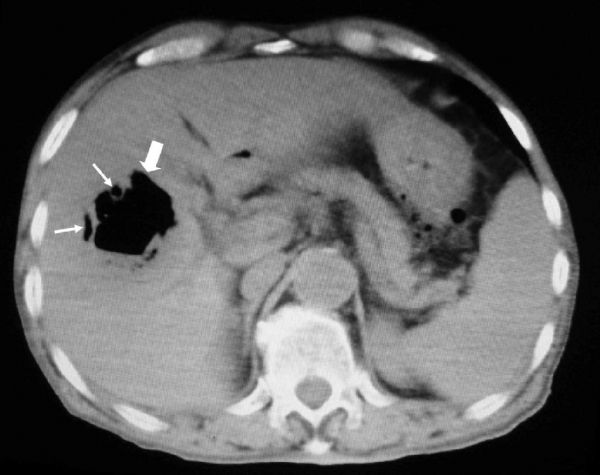

Kai Qu, Chang Liu, Aasef M A Mansoor, Bo Wang, Jincai Chen, Liang Yu, Yi Lv

Locally advanced colorectal cancer complicated with adjacent organic invasion may remain confined to the local area with minimal metastasis. In the present paper, we report on a patient with advanced right colon cancer, including liver, gallbladder, and duodenal invasion behind the scene of liver abscess. En bloc resection was performed on the patient, with right-hemicolectomy, cholecystectomy, partial duodental resection, and hepatectomy. Postoperative management was administered, including nutritional support in the early postoperative period, effective anti-infection treatment, and adjuvant chemotherapy (FOLFOX4). The patient survived for 16 months after the operation. Common clinical manifestations of colorectal cancer were digestive symptoms and changes in defecation. However, the clinical manifestation of locally advanced colon cancer was extremely complicated. Extended or multivisceral resection may offer patients a chance to survive an acute crisis and allow for treatment with adjuvant therapy.